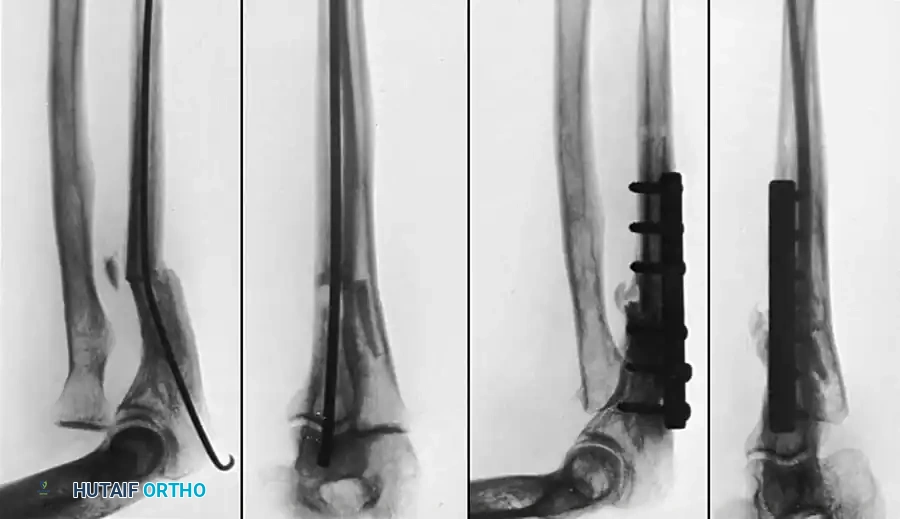

Fig. 55-29: (A) Malunited fracture of the shaft of the ulna with chronic dislocation of the proximal radius (Monteggia fracture). (B) Four months post-reconstruction involving ulnar osteotomy, application of a compression plate, and radial head excision with the fragmented bone used as autograft for the ulna. Excellent motion was restored.

Ulnar Osteotomy and Fixation:

* Make a second incision 7.5 cm long over the subcutaneous border of the posterior ulna.

* Perform an osteotomy of the ulna as near to the apex of the old fracture deformity as possible.

* Biomechanical Imperative: The ulna must be distracted and realigned to restore its anatomical length. Failure to restore ulnar length will result in recurrent subluxation of the radius.

* Fix the realigned ulna with a robust dynamic compression plate (DCP) or locking compression plate (LCP).

* Pack autogenous cancellous bone graft (often utilizing the excised radial head, fragmented into cancellous chips) around the ulnar osteotomy site to ensure rapid consolidation.